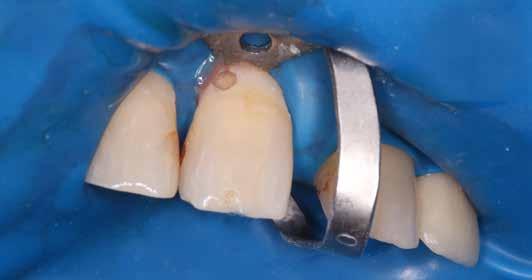

Kofferdám: ellenség vagy barát?

Véleményem szerint az abszolút izolálás elengedhetetlen kelléke a mai modern fogászatnak. Az izolálás ezen formája – számos előnyének köszönhetően – segítséget tud nyújtani mind az endodoncia, mind pedig a resturatív fogászat területén. Az előadásom fő célja, hogy meghozzam a kedvet a kofferdám használatához. Megerősítést szeretnék adni azoknak is, akik alkalmazzák, de bizonytalanok. Emellett tippekkel és trükkökkel is fogok szolgálni a hozzám hasonló fanatikusok számára, ezzel megkönnyítve a nehezebb esetek izolálását is.